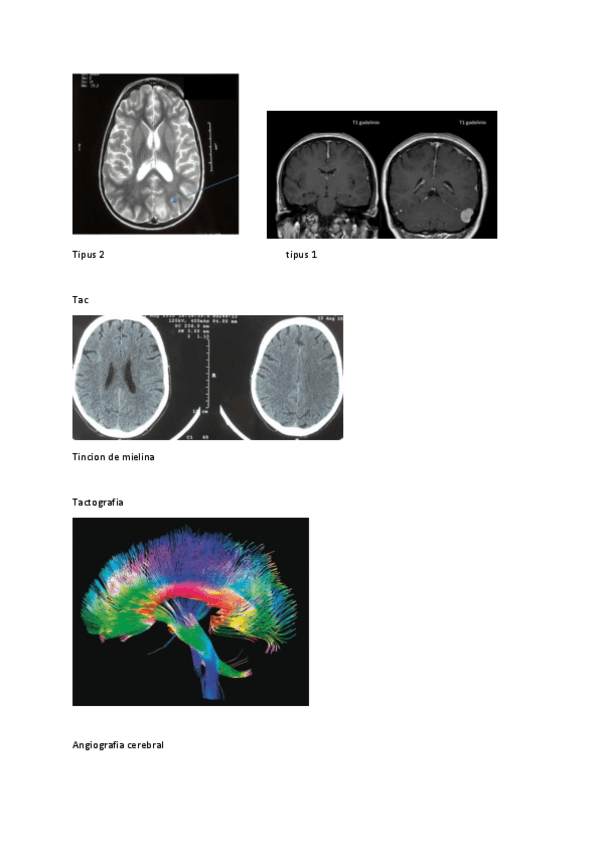

He publicado nuevos practicas de 1º Estructura y Función del Sistema Nervioso: Neuroimagen-anatomica-2024.docx.pdf